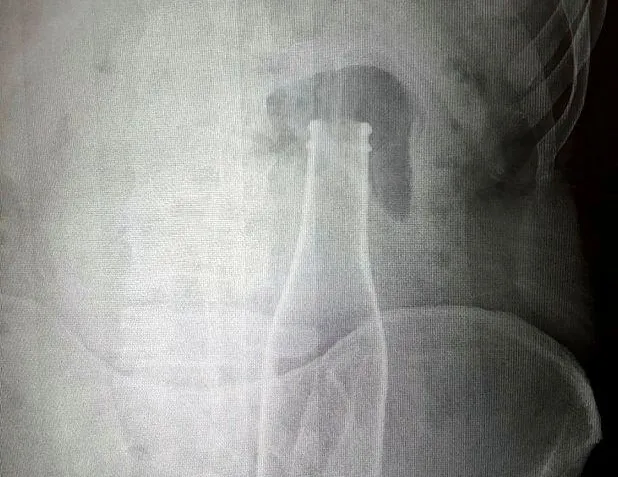

Vücudundan şişe çıkan genç: Yanlışlıkla oldu

Vücudundan şişe çıkan genç: Yanlışlıkla oldu Son dakika haberi... Karaman'da karın ağrısı şikayetiyle gittiği hastanede çekilen röntgen filminde kalın bağırsağında şişe olduğu ortaya çıkan Afgan A.E.'nin (27) ifadesinde, ''Olay günü banyoda duş alırken yanlışlıkla bu olay gerçekleşti'' dediği ortaya çıktı. Afgan genç, "Yaşanan olaydan dolayı kimseden şikayetçi değilim” dedi.